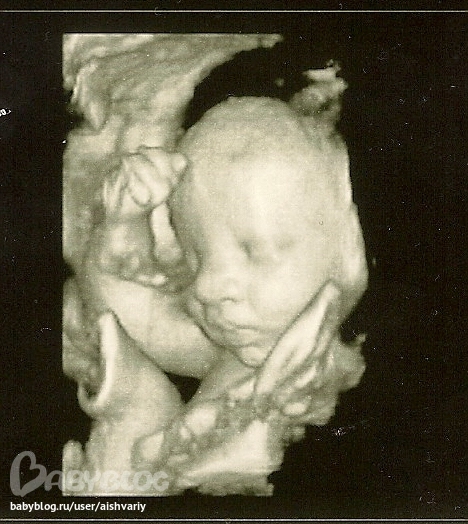

Результаты: УЗИ, КТГ, доплера, скринингаНеделю назад ходили на очередное узи, было так приятно увидеть малыша ждали с нетерпением когда же нам нам на узи. Увидели с мужем как он там ручками прикрываеться, всё пытался лицо руками прикрыть , но узистка поймала момент и сделала нам одну фотку. малыш уже хорошо подрос, вес его 2300 сказали нам что это хороший вес для этого срока. отправила нас сделать очередь на проверку околоплодных вод, якобы что то многовата у нас воды в животе. а так всё у нас ок.

это моё чудо.